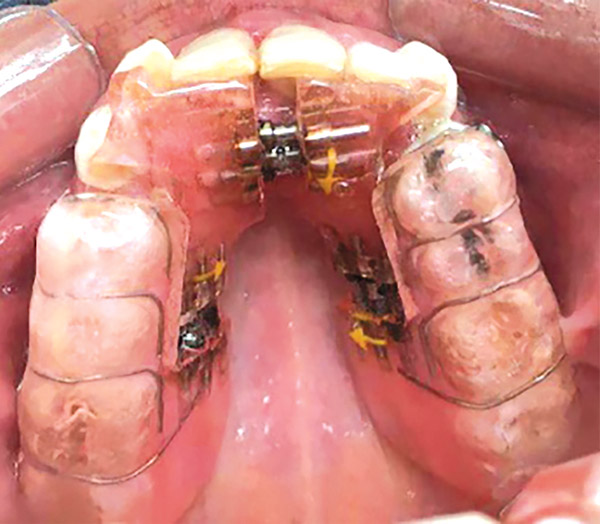

Se realizó una expansión dentoalveolar superior mediante un expansor con tornillo de 3 vías con efecto sagital y transversal, (Figura 9), preparación de la superficie dental para el bondeo de brackets por medio del arenado con partícula de sílice 60 μm a 40 lbs de presión con una angulación de 45° por un tiempo 3 a 4 segundos por diente, (Figura 10 y 11), y una fase ortodóncica con brackets prescripción Roth 0.022 x 0.028, tubos bondeables en 6's y 7's. Para la corrección del apiñamiento con alineación y nivelación utilizando una secuencia de arcos NiTi 0.014, 0.016 0.020 superior e inferior, NiTi 0.017 x 0.25 acero 0.018, 0.020 superior e inferior y stripping antero inferior. Para obtener la clase II molar y canina bilateral con mecánica de elásticos dobles bilaterales clase II largos con elásticos 1/8 6 ½ oz y stripping postero superior, para la corrección de la línea media con el uso de elásticos de línea media de 3/16 6 ½oz. La obtención del adecuado overjet y overbite se logró mediante el stripping, las cadenas intramaxilares y elásticos intermaxilares. Se obtuvo la máxima intercuspidación, paralelismo radicular y oclusión funcional en la fase de detallado mediante arcos de acero 0.017 x 0.025 y 0.019 x 0.025 superior e inferior, con dobleces de primer, segundo y tercer orden; restauración protésica en los dientes con fluorosis se trabajó mediante el tallado, la toma de impresiones, (Figura 10 y 11) y la colocación de la resina termocurada.

Figura 9. Aparato expansor.